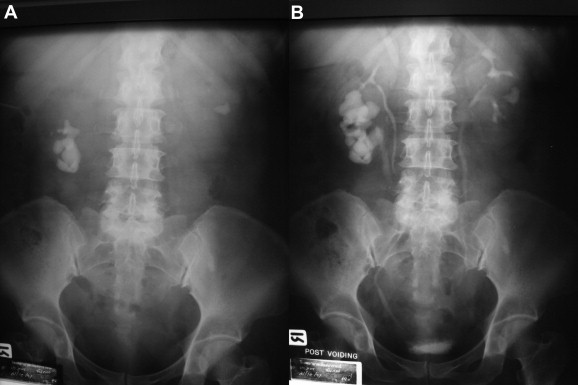

A 49-year-old woman presented with right flank pain and the sporadic spontaneous passing of small stones. She had had these symptoms for 3 years. She had no history of urinary tract infection or hematuria. A physical examination revealed an old surgical scar from a cesarean section. She was obese with a body mass index (BMI) of 32.03 kg/m2. Neither kidney was palpable. The plain film showed staghorn calculi in the right kidney and a 1.5 cm calcification in the middle caliceal stone of the left kidney. The intravenous urography demonstrated a partial duplication of the right kidney, a full staghorn stone in the lower moiety with moderate hydronephrosis, and mild delayed excretory function as shown in Fig. 2. The left renal calcification was a middle caliceal stone with localized caliectasis.

(A) Double collecting system of right kidney with staghorn calculi in lower ...

Figure 2.

(A) Double collecting system of right kidney with staghorn calculi in lower moiety and (B) left middle caliceal stone.